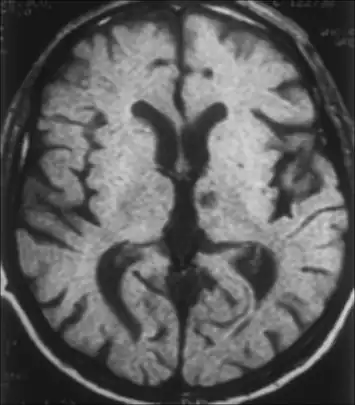

Left subthalamic nucleus stroke caused contralateral hemiballism. -